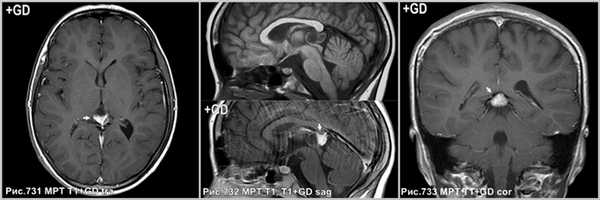

На КТ и МРТ солидные компоненты интенсивно накапливают контраст [34,43,49,53,130].

Интенсивное контрастирование солидных участков пинеоцитомы (стрелки на рис.731-733).

- Нейровизуализация. КТ, МРТ головного мозга визуализуют новообразование пинеальной локализации, выявляют окклюзию опухолью сильвиева водопровода, гидроцефалию. Пинеоцитома отличается чёткими контурами, при контрастировании — интенсивным гомогенным накоплением контрастного вещества. Отсутствие возможности проведения томографических исследований является показанием к эхоэнцефалографии, позволяющей определить объёмное образование по смещению серединного эхо-сигнала.